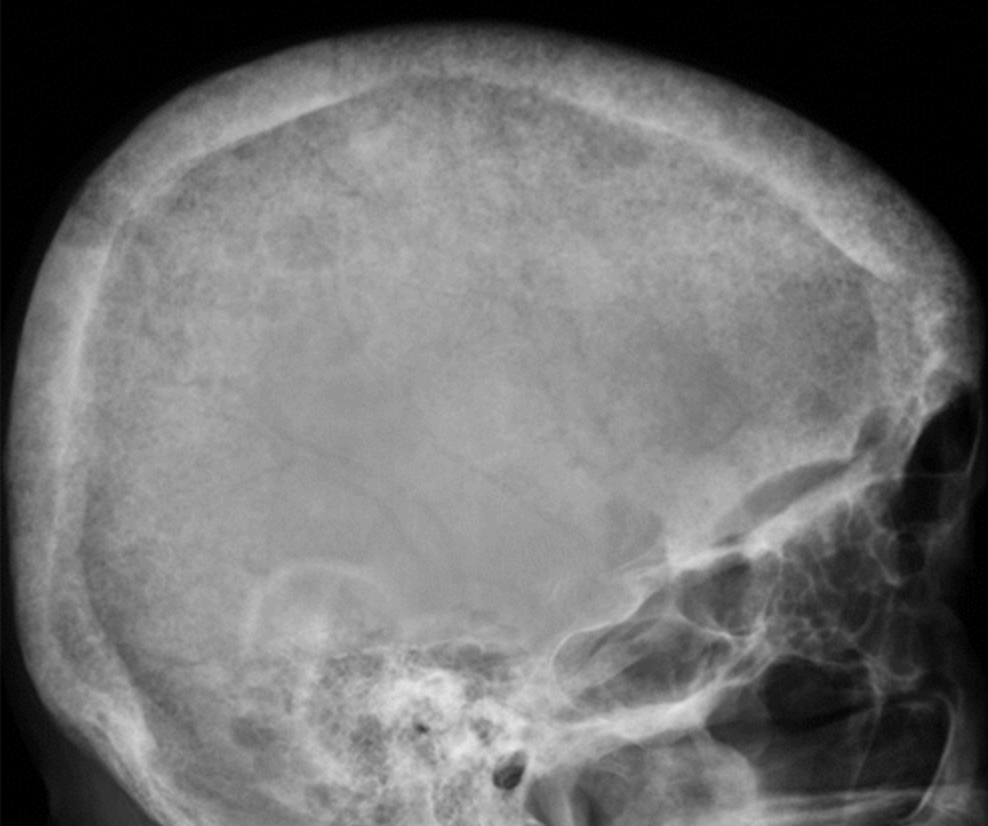

SALT AND PEPPER SKULL

Salt And Pepper Appearance Radiology . Salt and pepper appearance of the skull (sometimes called, pepper pot skull), bone cysts, brown tumors of long bones, and subperiosteal resorption of the distal phalanges are usual radiological features of osteitis fibrosa cystica. “pepper” appearance due to flow voids. In this case, a young male patient with hypovitaminosis d and secondary hyperparathyroidism, radiological features. T1wi salt and pepper appearance: Five different infiltration patterns have been described on mri with the “salt. “salt” appearance secondary to subacute hemorrhage. The salt and pepper appearance, first described in 1987 by olsen et al, is a characteristic imaging feature of paragangliomas, found on t1 and t2 mri sequences, reflecting its hypervascular.

Salt and pepper sign of the calvaria refers to multiple tiny Salt And Pepper Appearance Radiology Salt and pepper appearance of the skull (sometimes called, pepper pot skull), bone cysts, brown tumors of long bones, and subperiosteal resorption of the distal phalanges are usual radiological features of osteitis fibrosa cystica. In this case, a young male patient with hypovitaminosis d and secondary hyperparathyroidism, radiological features. “salt” appearance secondary to subacute hemorrhage. Five different infiltration patterns have. Salt And Pepper Appearance Radiology.